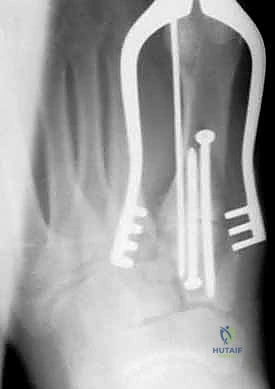

1. الرد المفتوح والتثبيت الداخلي (ORIF - Open Reduction and Internal Fixation)

هذا هو الإجراء الكلاسيكي والأكثر شيوعاً. يهدف إلى إعادة العظام إلى مكانها الطبيعي (الرد) وتثبيتها باستخدام معدات طبية (مسامير، شرائح، أو أسلاك) حتى تلتئم الأربطة والعظام.

خطوات العملية:

1. التخدير: يتم إجراء الجراحة تحت التخدير الموضعي (النصفي) أو العام.

2. الشق الجراحي: يقوم الدكتور هطيف بعمل شق جراحي دقيق (أو شقين) على ظهر القدم للوصول إلى المفاصل المصابة، مع الحرص الشديد على حماية الأعصاب والأوعية الدموية الدقيقة في تلك المنطقة باستخدام مبادئ الجراحة المجهرية.

3. التنظيف والرد: يتم تنظيف المفاصل من أي شظايا عظمية أو أنسجة محشورة تمنع عودة العظام لمكانها. ثم يتم إعادة العظام بحذر شديد إلى محاذاتها التشريحية الدقيقة (القوس الروماني).

4. التثبيت (Fixation): يتم تثبيت العظام باستخدام مسامير معدنية خاصة (Solid or Cannulated Screws) تعبر المفاصل لتثبيتها بإحكام. في بعض الحالات، يتم استخدام شرائح معدنية صغيرة للحفاظ على الاستقرار.

5. مسمار ليزفرانك: الخطوة الأهم هي وضع "مسمار ليزفرانك" (Lisfranc Screw) الذي يمر من العظم المسماري الإنسي إلى قاعدة المشط الثاني، لتعويض وظيفة الرباط الممزق.

6. الإغلاق: يتم إغلاق الشقوق الجراحية بعناية تجميلية ووضع القدم في جبيرة لحمايتها.